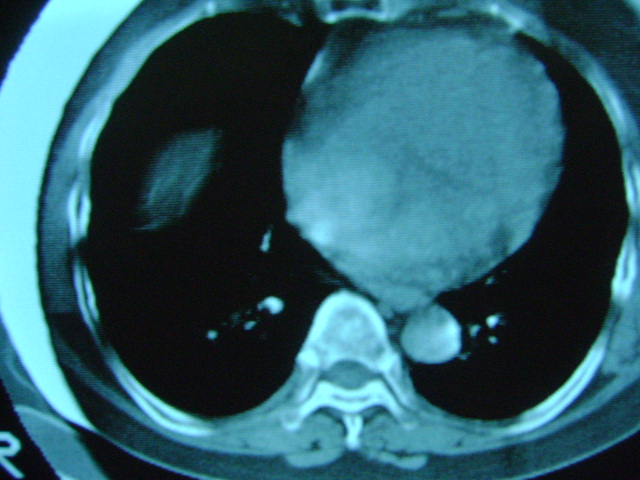

朋友的母亲,56y,咳嗽三个月,感觉左肺门不对,请大家给点意见

心功能不全肺淤血

老年人,肺动脉略迂曲